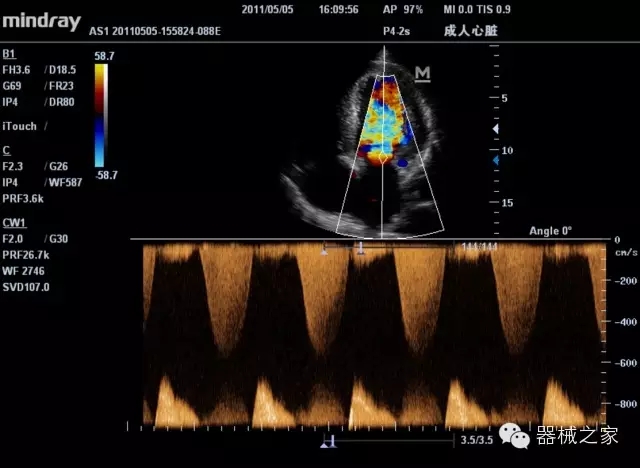

經(jīng)典產(chǎn)品:M7(星鉆)

臨床圖片賞析

產(chǎn)品特點(diǎn)

·裝載有采用Multi-Core多核處理的非嵌入式平臺(tái),成像效率大大提高,并且能夠給用戶帶來高速、多任務(wù)并行信號(hào)處理體驗(yàn);

·優(yōu)秀的圖像效果、強(qiáng)大的功能體驗(yàn)、豐富的探頭選擇、合理的便攜式設(shè)計(jì),全中文顯示及病人管理界面,使得M7在任何場合、任何時(shí)候都能快速響應(yīng)更好的心血管、腹部、婦產(chǎn)、小器官等常規(guī)超聲檢查以及肌骨、神經(jīng)、顱腦、術(shù)中等新興領(lǐng)域的使用需求;

8倍波束并行處理系統(tǒng)

·在便攜式緊湊平臺(tái)上采用更多倍波束并行接收信號(hào)處理模式,無論二維還是彩色血流圖像狀態(tài)下,擁有更靈敏的回波頻移捕獲能力,大大提高時(shí)間分辨率,尤其使得心血管表現(xiàn)更為突出;